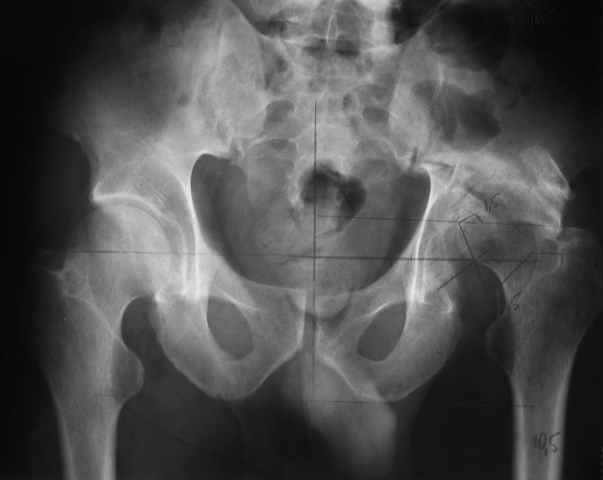

I think, if symphysis is unstable at first you must open and stabilize symphysis by plate or

external fixator or may be use both together.

Our experience showes, that reposition and stabilization pelvis in zone of old acetabular fractures with bone grafting are very traumatic and not effective due head AVN and hip arthrosis.